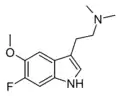

Substituted tryptamines, or serotonin analogues, are organic compounds which may be thought of as being derived from tryptamine itself. The molecular structures of all tryptamines contain an indole ring, joined to an amino (NH2) group via an ethyl (−CH2–CH2−) sidechain. In substituted tryptamines, the indole ring, sidechain, and/or amino group are modified by substituting another group for one of the hydrogen (H) atoms.

| Chemical structure | Short Name | Origin | Ring Substitution | RN1 | RN2 | Full Name | CAS Number |

|---|---|---|---|---|---|---|---|